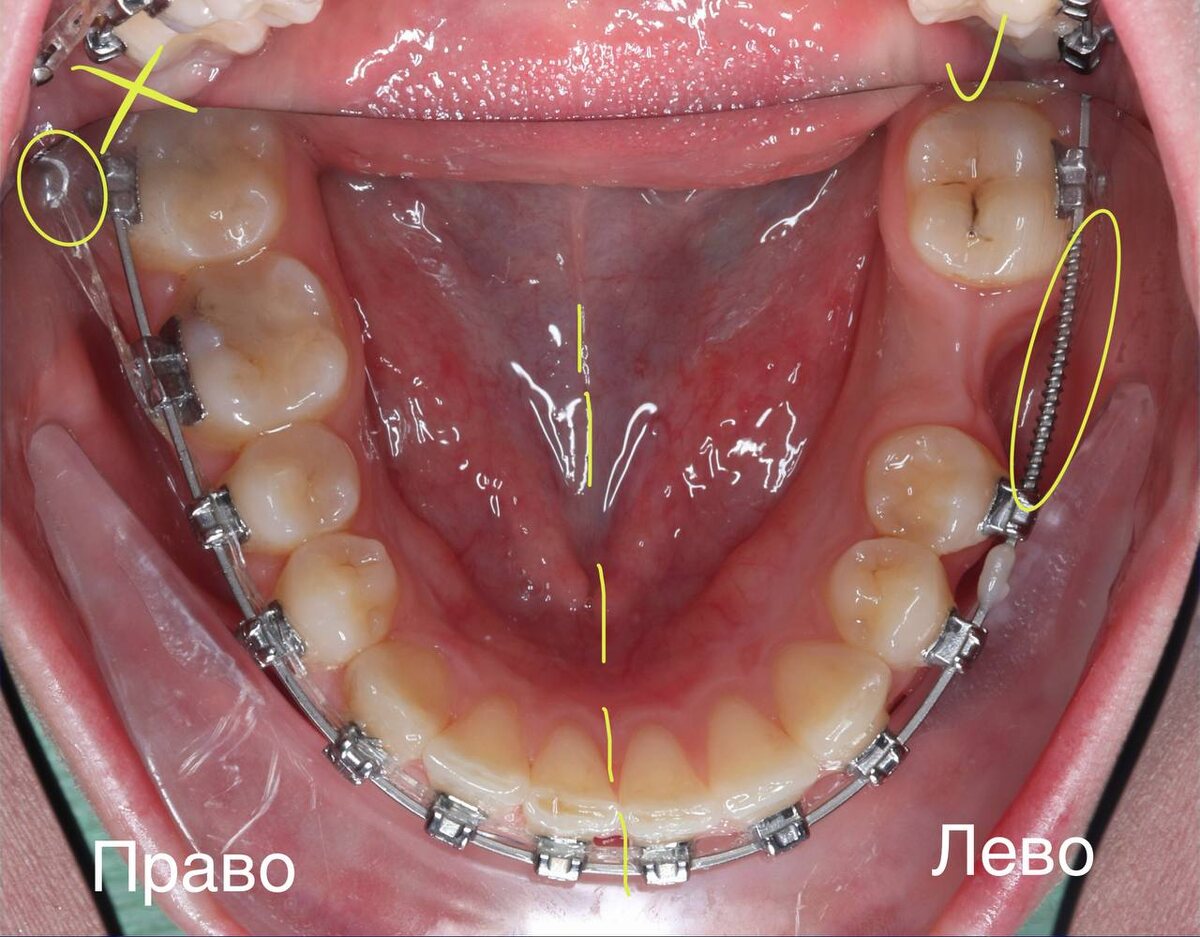

: Справа удалили, чтобы поставить винт и тянуть зубы назад с коррекцией центра нижнего зубного ряда. Слева не удаляла, чтобы была дополнительная опора для коррекции центра нижнего зубного ряда и выравнивания дистопированного премоляра. 8ку в какой-то момент даже подключила к брекет-системе для доп опоры😱